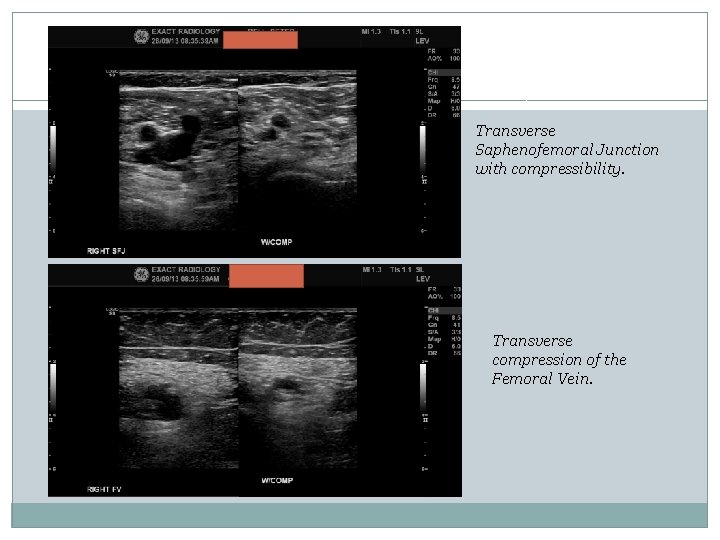

Transverse Saphenofemoral Junction with compressibility. Transverse compression of the Femoral Vein.